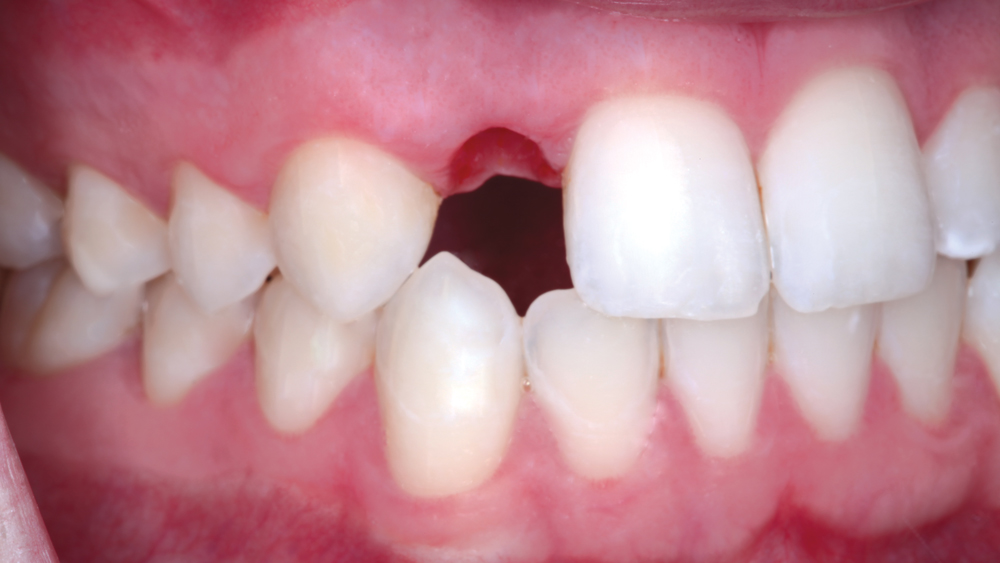

The following case illustrates the efficient, straightforward clinical workflow for placing Hahn Tapered Implants via guided surgery. A digital treatment plan is developed in which a 3.5 mm implant is positioned to support the ideal prosthetic outcome. An immediate provisional crown is designed in concert with the surgical guide and delivered at the time of surgery, helping to produce a predictable, highly esthetic restoration for a demanding case in the smile zone.